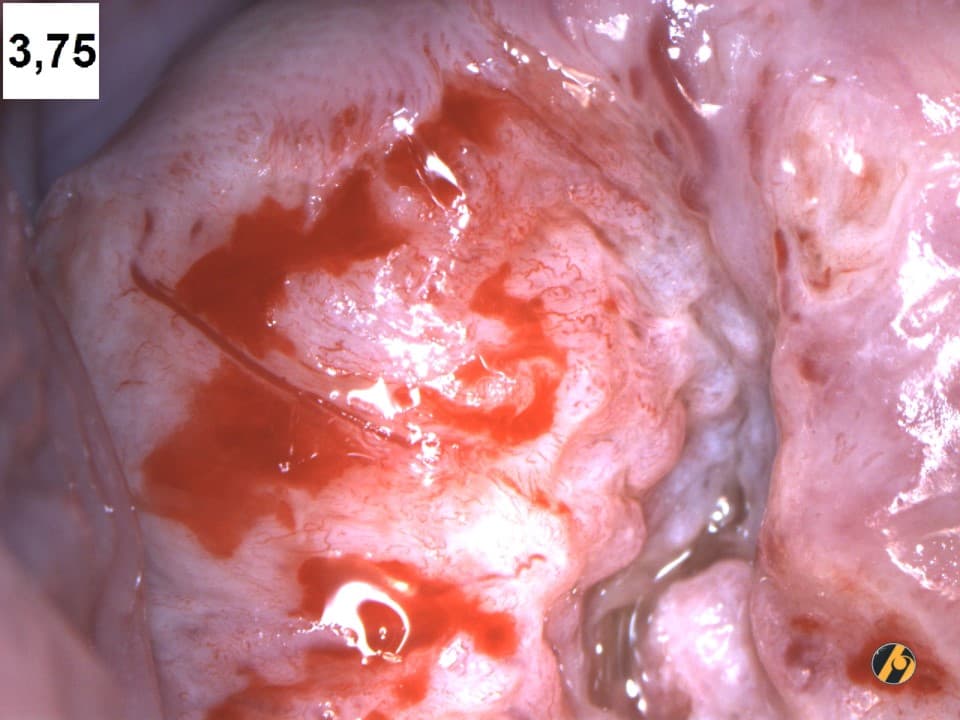

- kolposkopije: metoda promatranja površine cerviksa uz povećanje od 6 - 40 puta;

- biopsije: ciljano uzimanje isječka sa sumnjivih dijelova cerviksa uz histološku analizu i